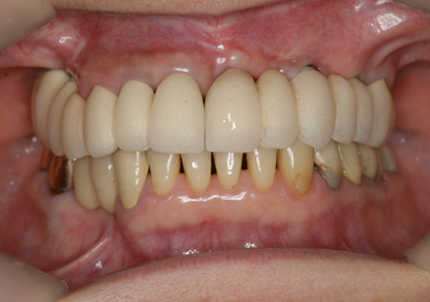

23.口腔内写真(2024年6月26日)

25.初診より18年経過(2024年6月26日)